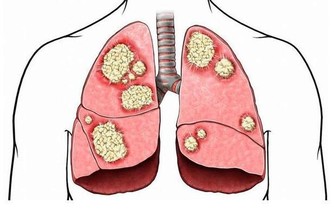

2、戒菸限酒

經常吸煙不僅會提高罹患肺癌、哮喘的風險,還會顯著降低人體免疫力。而酗酒除會引發酒精中毒外,同樣會削弱人體的免疫功能。